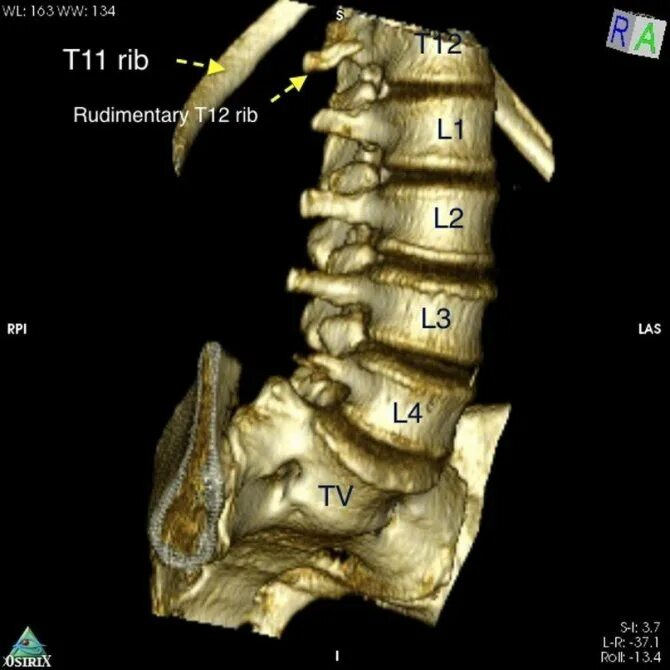

Гипоплазия 12 пары ребер